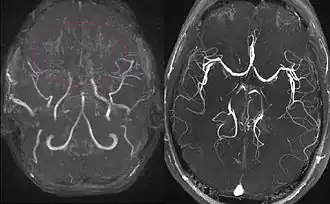

Right: healthy patient, for comparison.

Cerebral angiography is the gold standard of diagnosing moyamoya disease and its progression. According to Suzuki's system, it can be classified into six stages:[12]

- Stage 1 Narrowing of carotid fork

- Stage 2 Initiation of the moyamoya and dilatation of intracranial main arteries

- Stage 3 Intensification of the moyamoya and defects of the anterior cerebral artery and middle cerebral artery

- Stage 4 Minimization of the moyamoya and defects of the posterior cerebral artery

- Stage 5 Reduction of the moyamoya and development of external carotid artery collaterals

- Stage 6 Disappearance of the moyamoya and circulation only via external carotid artery and vertebral artery

Magnetic resonance angiography (MRA) is also useful in diagnosing the disease with good correlation with Suzuki's grading system.[12]